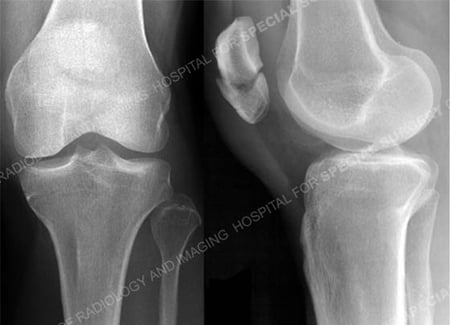

Anteroposterior and lateral radiographs revealing a transverse patella fracture.